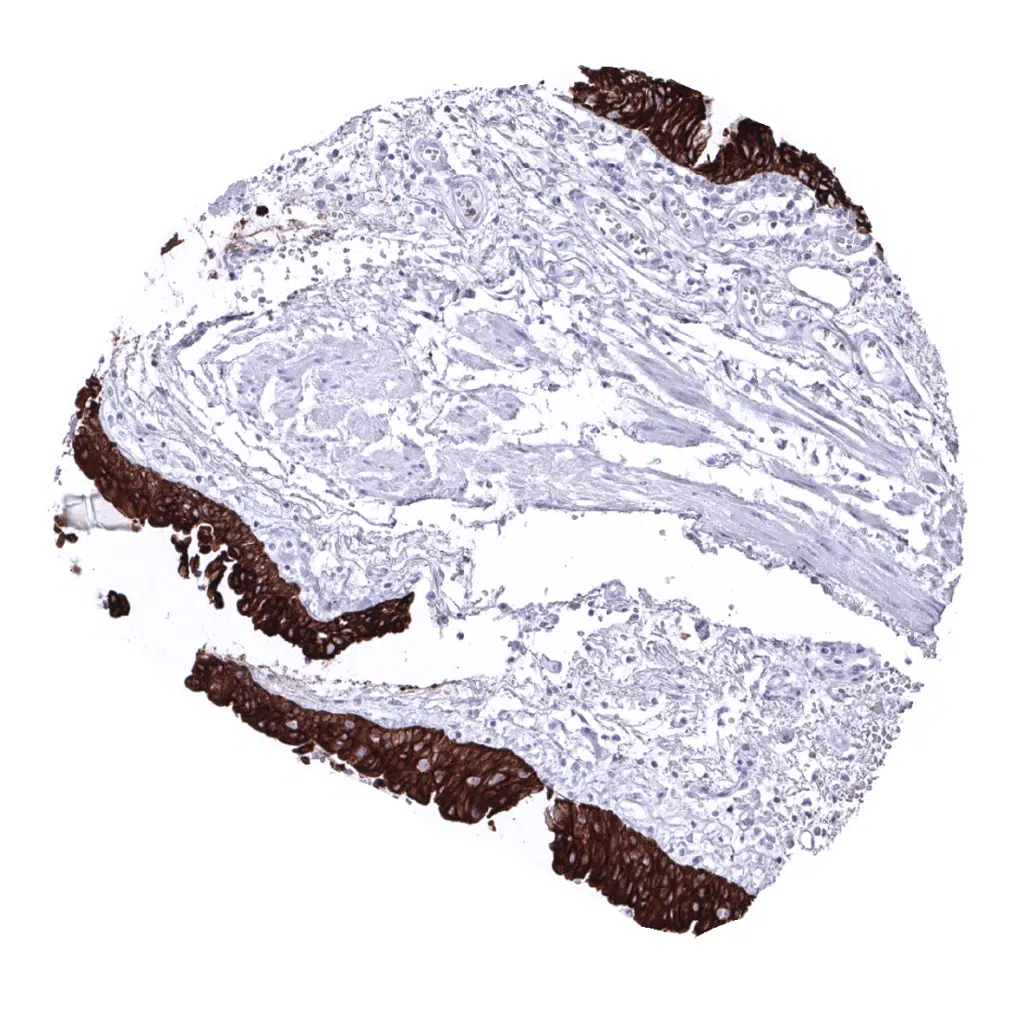

Skin